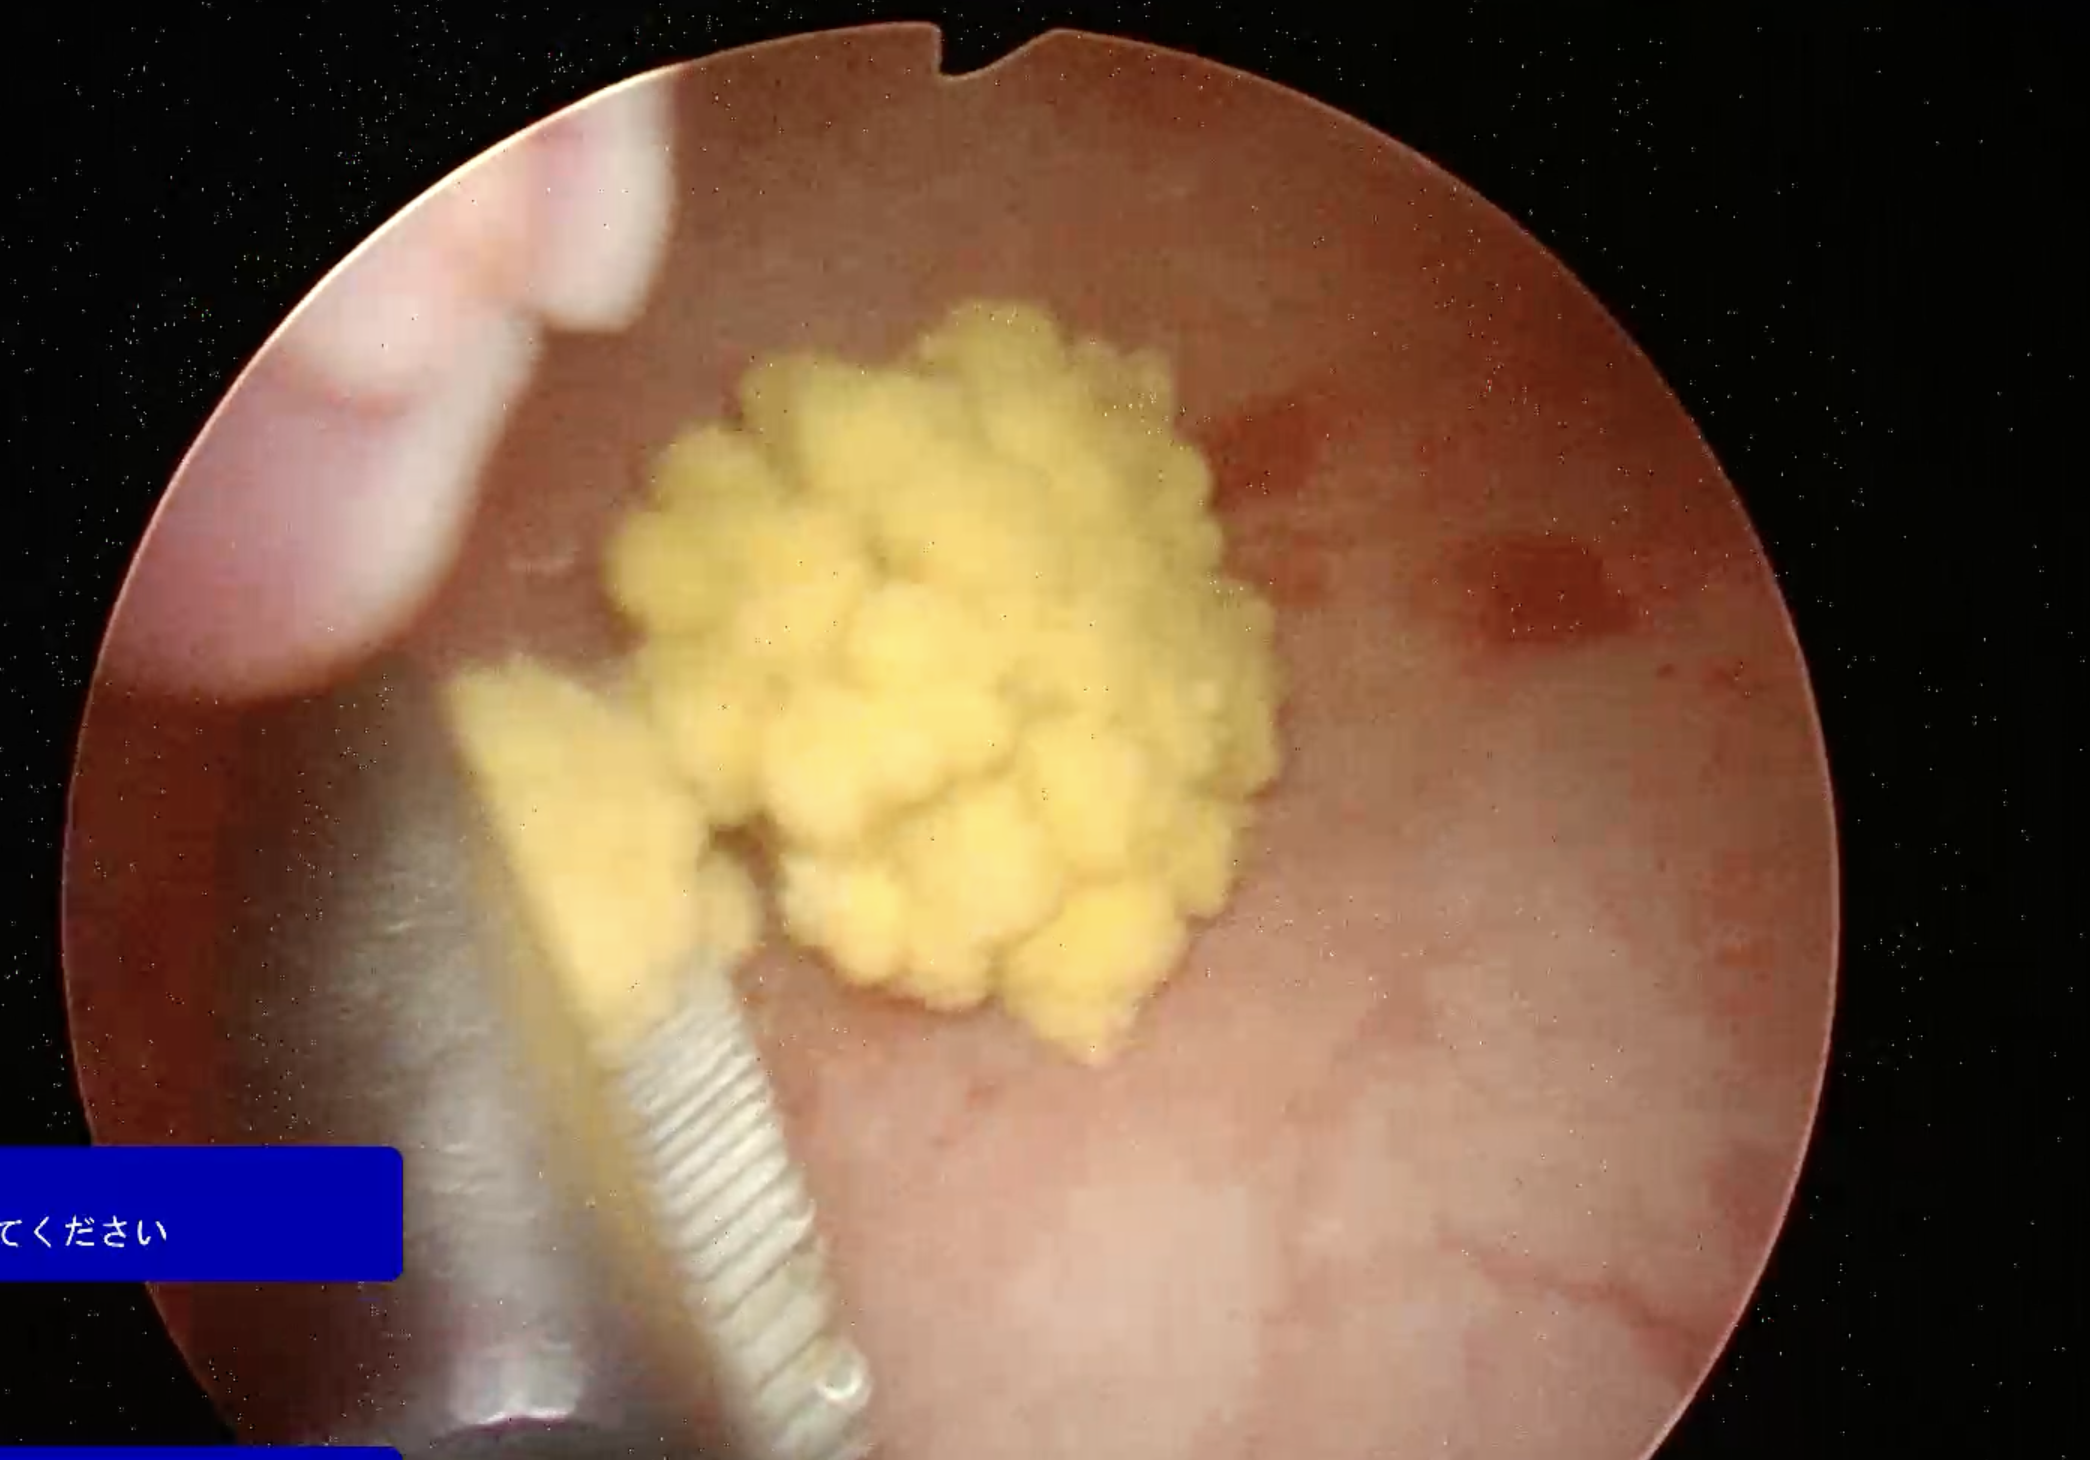

当院では、腹腔鏡を使用することで手術の際にお腹を切らずに一部穴を開けるだけで、結石を取ることが可能です。

しかも腹腔鏡のスコープでは膀胱の内部をくまなく見ることができるため、かなり細かい結石であっても目視して取り出せるため、石の取り残しのリスクが大幅に減少します。

以下に写真を載せてあります。